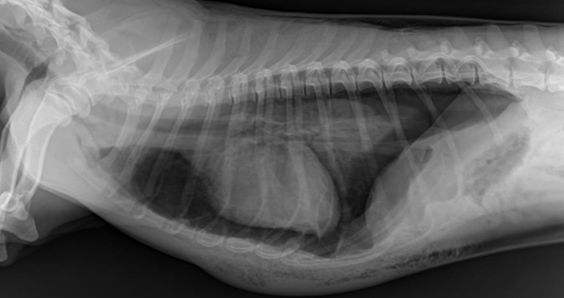

![]() | * 종격동의 정상 크기 - 척추뼈의 2배 정도 공간 - 고양이는 더 홀쭉함 |

![]() | - 종격동이 2배 이상 커지고, 기관이 휘어졌는데.. - 종양 때문일 수도 있지만, - 이건 살이 너무 많이 쪄서.. |